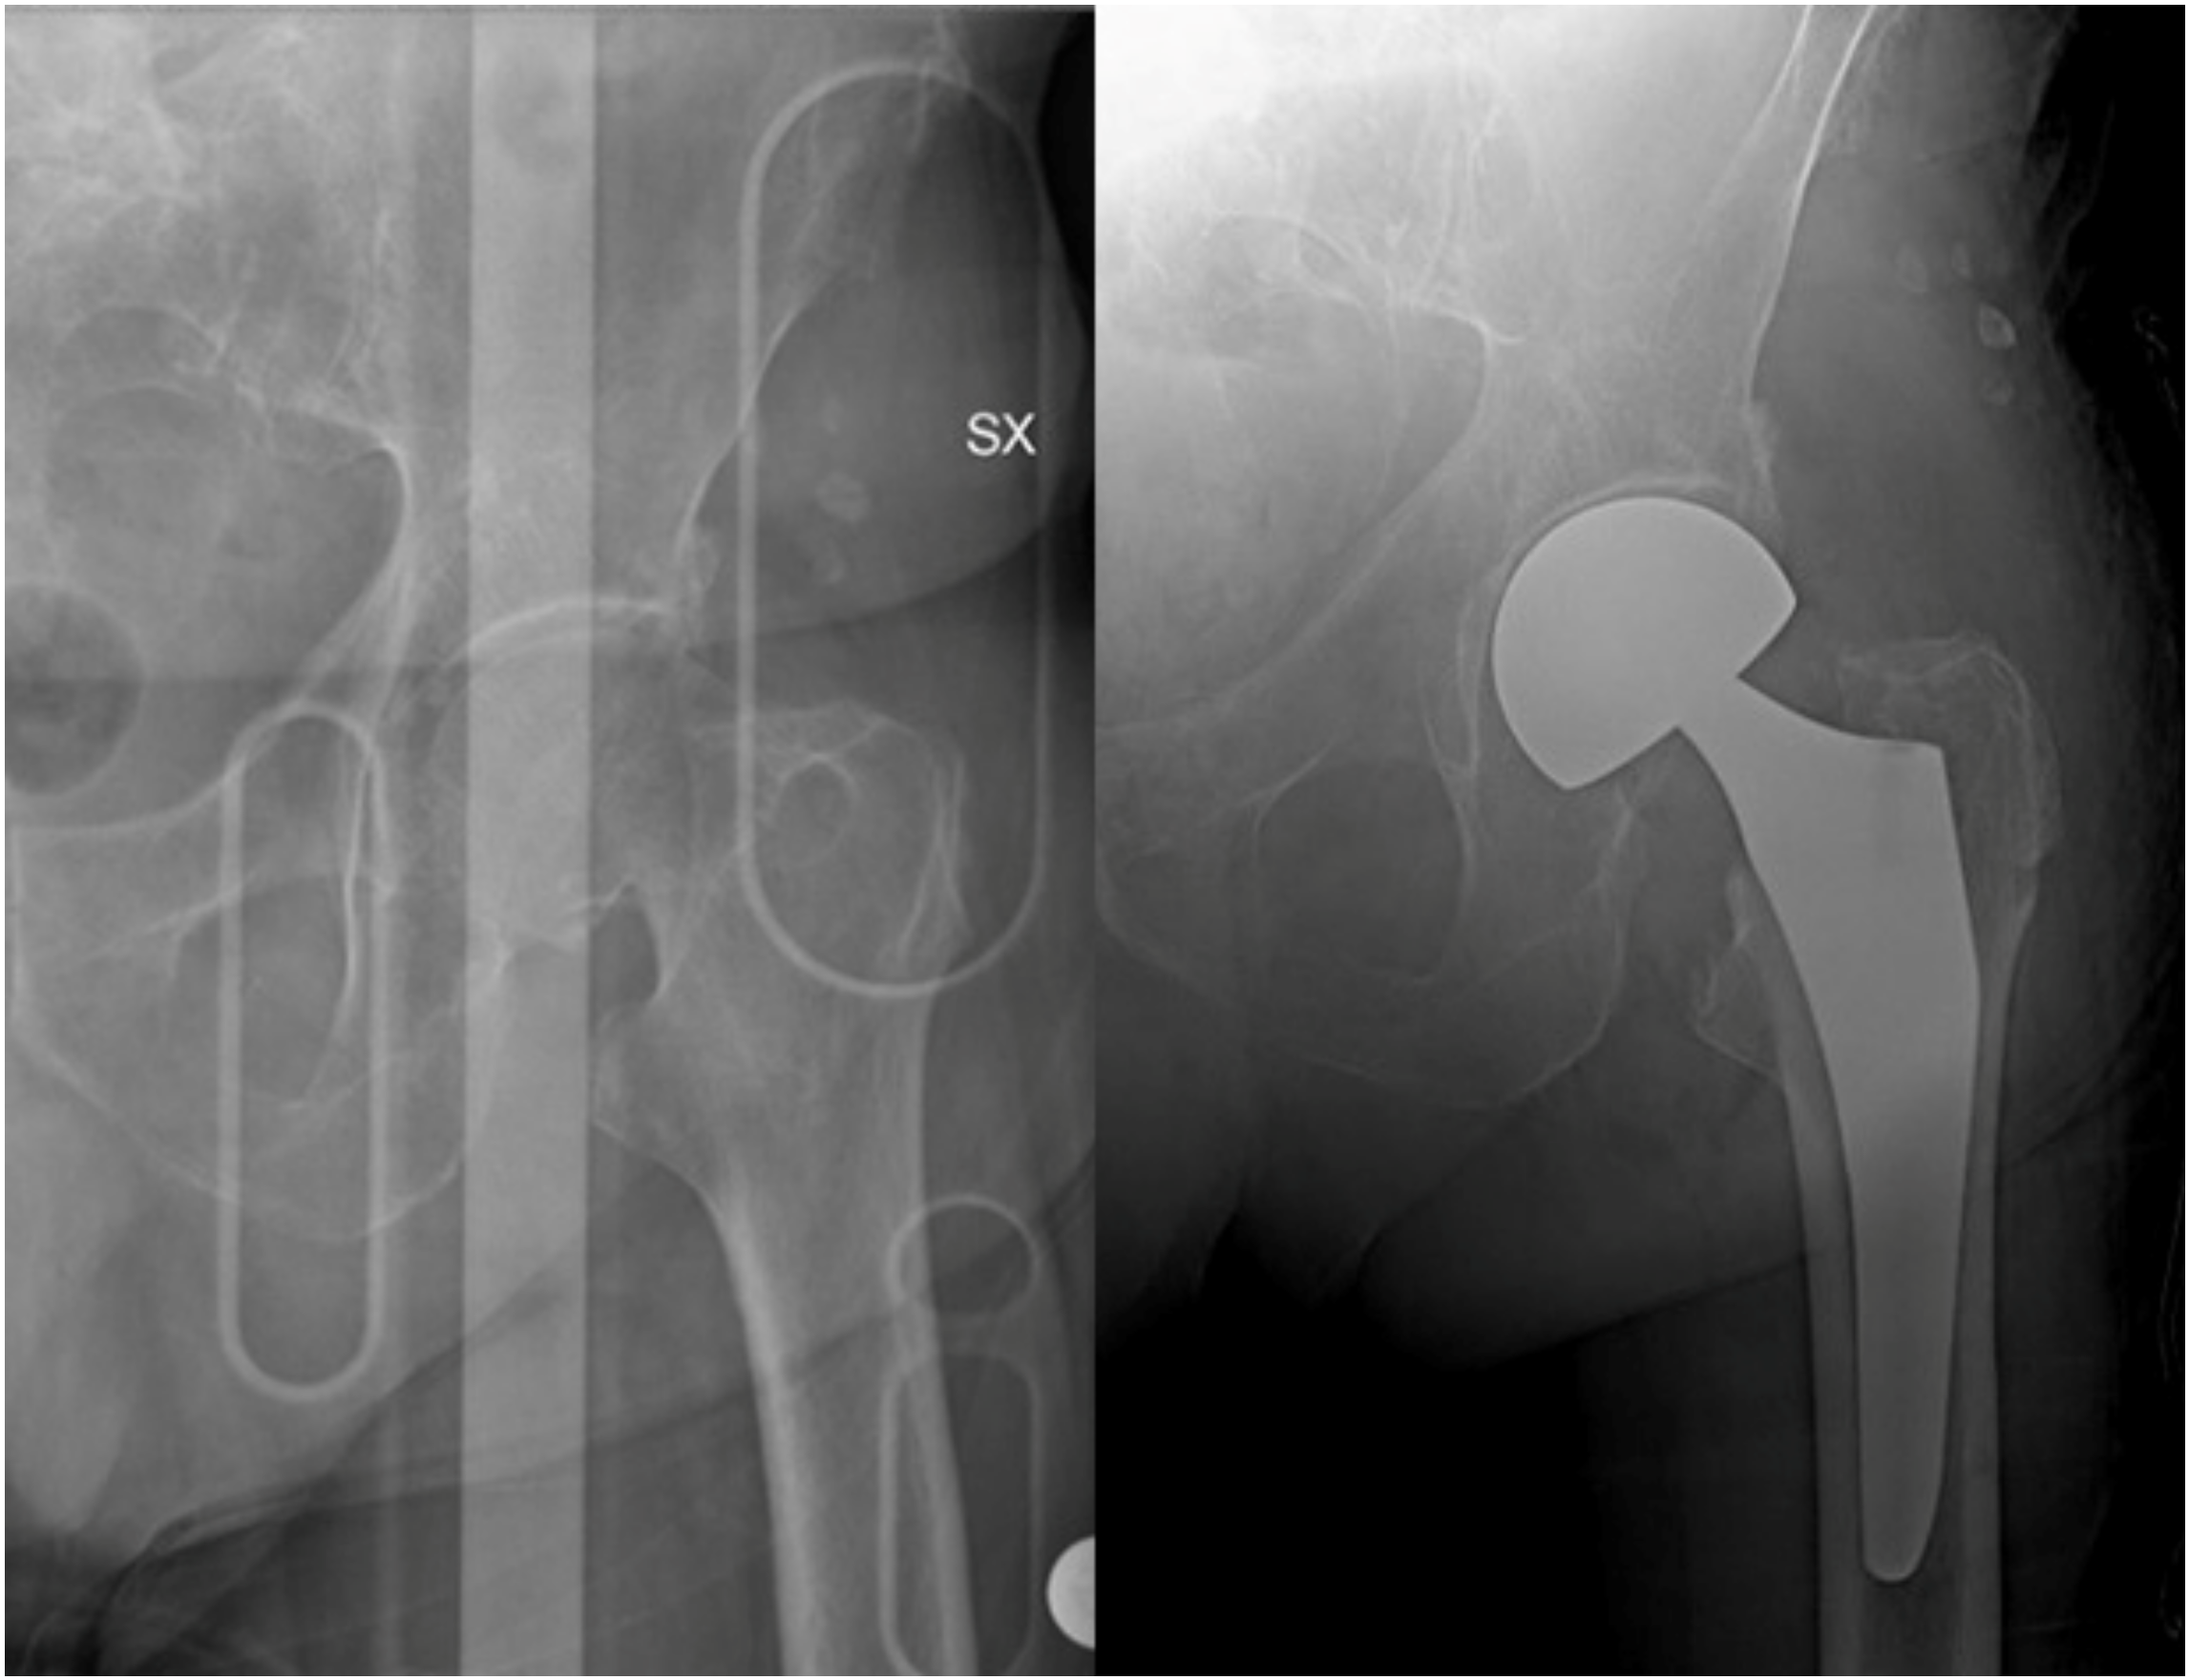

- Parker, M.J.; Gurusamy, K.S.; Azegami, S. Arthroplasties (with and without bone cement) for proximal femoral fractures in adults. Cochrane Database Syst. Rev. 2010, 16, CD001706. [Google Scholar] [CrossRef]

- Braun, K.F.; Hanschen, M.; Biberthaler, P. Frakturendoprothetik der medialen Schenkelhalsfraktur. Der Unfallchirurg 2016, 119, 331–345. [Google Scholar] [CrossRef]

- Rozell, J.C.; Hasenauer, M.; Donegan, D.J.; Neuman, M. Recent advances in the treatment of hip fractures in the elderly. F1000Res 2016, 5, 1953. [Google Scholar] [CrossRef] [PubMed]

- Konow, T.; Baetz, J.; Melsheimer, O.; Grimberg, A.; Morlock, M. Factors influencing periprosthetic femoral fracture risk. Bone Jt. J. 2021, 103-B, 650–658. [Google Scholar] [CrossRef] [PubMed]